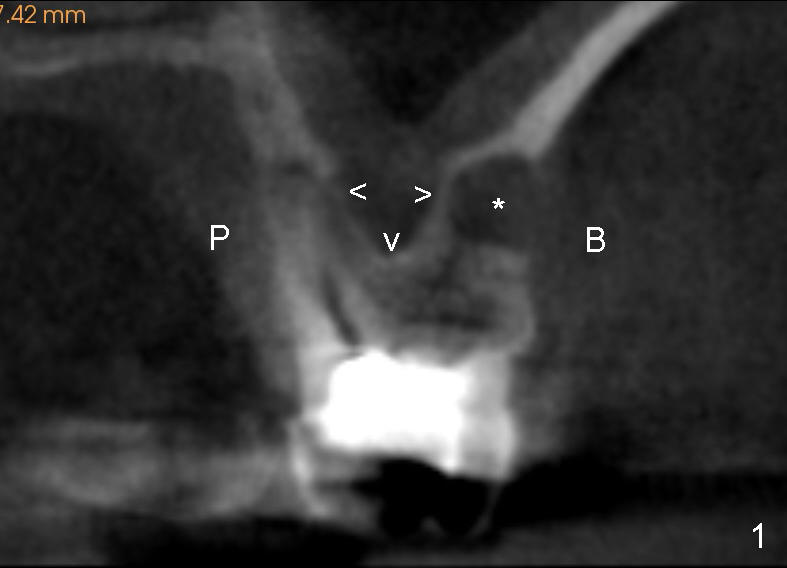

Fig.1 is a CBCT coronal section of the tooth #14. It shows that the sinus floor (arrowheads) extends coronally between roots (P: palatal; B: buccal). *: apical radiolucency associated with the mesiobuccal root.